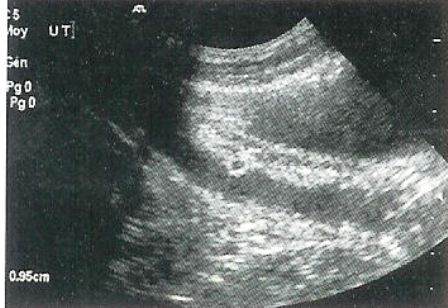

Typischer Ultraschallbefund einer vorzeitigen embryonalen Resorption. Bei dieser Hündin wurde eine Infektion der Gebärmutter festgestellt.